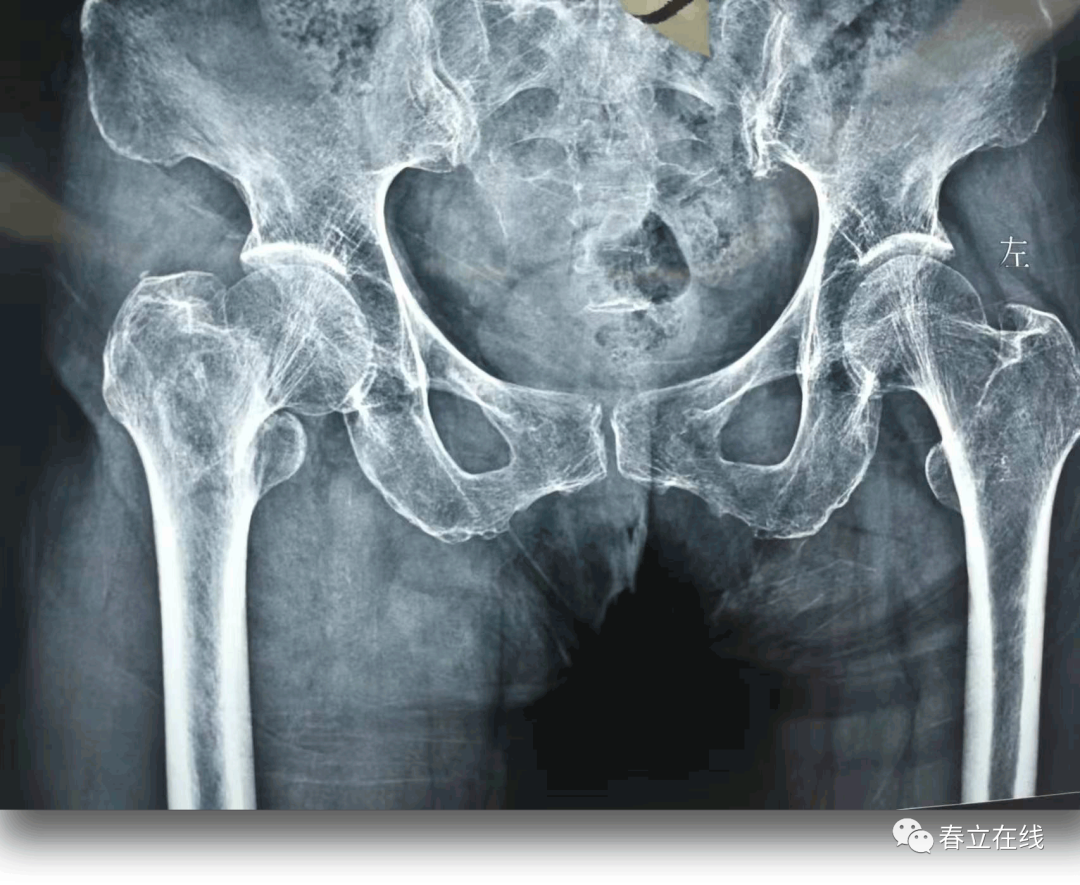

髋部疼痛( );左髋关节主,被动活动受限,活动时可触及骨擦感及反常活动